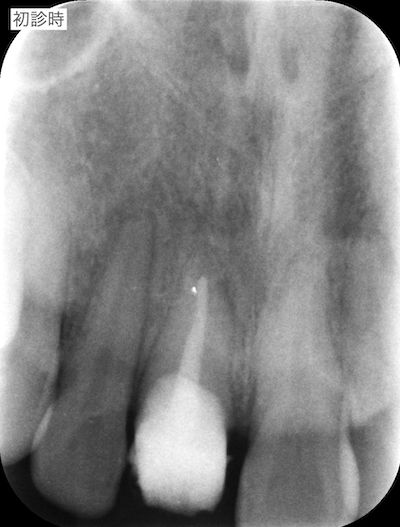

コンポジットレジンで歯冠部が作られていました。歯肉縁下まで及んでいたので、いったん全て外して、状況を確認した方が良いことを説明しました。患者さんも歯肉のラインが気になっておられ、前歯の形も理想ではないとのことだったので、全て外して仮歯の作成を行うことを説明し、同意頂けました。

旧仮歯を撤去したところ、歯根が一部水平的に破折していました。歯肉のラインが歪になっていたのはこのことが原因であったと説明しました。支台築造を行い、仮歯を作成しました。患者さんはホワイトニングを希望しておられたので、ホームホワイトニングを行ったのちに周りの歯の色に合わせてセラミック冠を作成することで同意頂いたので、ホームホワイトニングを行いました。